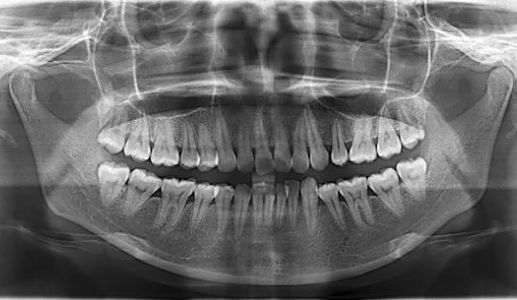

首先,正规的牙齿矫正治疗,在治疗前要做完善的检查[临床检查、数码全景片、侧位片、牙齿模型分析、照片采集等]。结合患者口腔情况及要求,设计出详细的矫治方案。如需要拔牙及补牙的患者需要在矫正前先进行处理,需要计划出时间。

据调查研究,86%的牙齿畸形儿童有不同程度的自卑感,89%的人(包括成年人)不敢在公众场合大声笑,而且畸形牙对儿童的口腔和身体健康造成很大的危害。矫正牙齿,成人要做,儿童更要做。